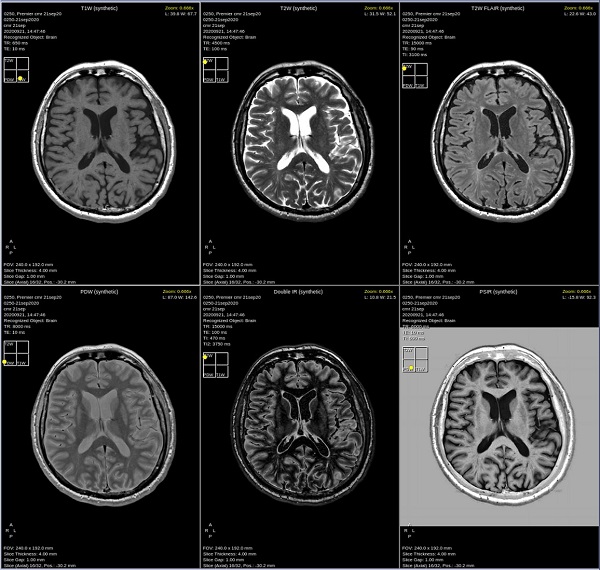

- By default, a 6-viewport display is launched with 6 unique MAGiC images.

Figure 3. 6-viewport display